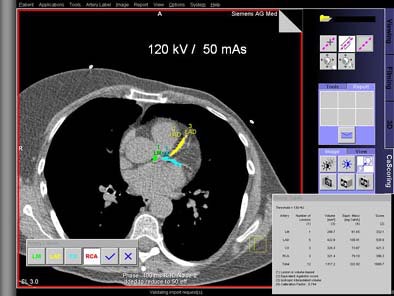

"Since you can’t scan those patients multiple times, we used a software platform to add artificial image noise," Schoepf said. The Vamp syngo Explorer application was applied to the resulting images to simulate reduced mAs of 150, 130, 110, 90, 70, and 50 in consistent regions of interest over the left ventricle. All three methods of calcium scoring were again applied in the usual manner at all noise degradation levels. Scoring variations at low-dose settings were again compared to those at the full dose, he said.

| Top, patient was scanned with 120 kVp/170 mAs. Below, artificial image noise was added using the Siemens Vamp syngo Explorer to simulate acquisition with lower dose settings at 120 kV/110mAs and 120kV/50 mAs. Calcifications in the left main coronary artery are highlighted in green, those in the left anterior descending coronary artery in yellow, and those in the left circumflex coronary artery in blue. The calcium scores at the three dose settings are not significantly different. Images courtesy of Dr. Joseph Schoepf. |